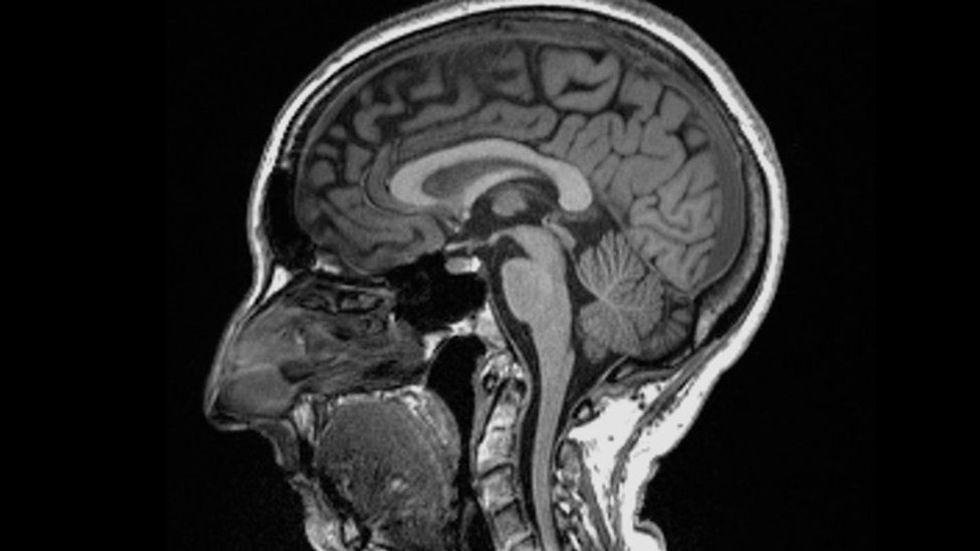

Ky studim zbuloi se truri i atyre që kishin Covid-19, kishte një humbje më të madhe të lëndës gri dhe anomali në indet e trurit, krahasuar me ata që nuk kishin COVID-19. Shumë nga ato ndryshime ishin në zonën e trurit të lidhura me shqisën e nuhatjes.

Douaud shpjegoi se është normale që njerëzit të humbin 0.2% deri në 0.3% të lëndës gri çdo vit në zonat e trurit që lidhen me kujtesën ndërsa plaken, por në vlerësimin e studimit, njerëzit që ishin infektuar me coronavirus humbën një shtesë. 0.2% deri në 2% të indeve krahasuar me ata që nuk ishin infektuar.

Përveç imazherisë, pjesëmarrësit u testuan për funksionin e tyre ekzekutiv dhe njohës duke përdorur Testin e krijimit të gjurmëve, një mjet i përdorur për të ndihmuar në zbulimin e dëmtimeve njohëse të lidhura me demencën dhe testimin e shpejtësisë dhe funksionit të përpunimit të trurit të një personi. Studiuesit zbuluan se ata që kishin humbjen më të madhe të indeve të trurit dolën edhe më keq në këtë provim.

Megjithëse zonat e trurit më të prekura duket se janë të lidhura me sistemin e nuhatjes, Douaud tha se nuk ishte e qartë pse ishte kështu.